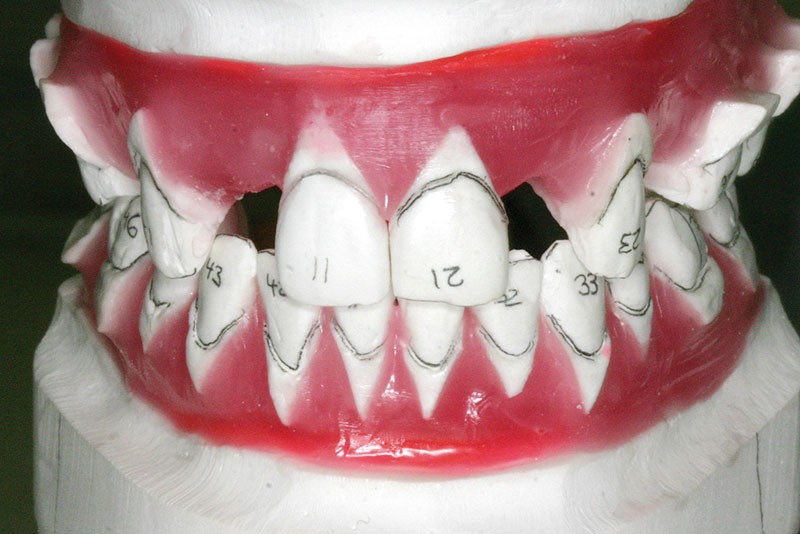

Un set-up est réalisé, il permettra de valider le plan de traitement avec les différents intervenants (fig. 14, 15).